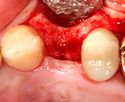

The implant fixture is turned into the osteotomy. Ideally, it is completely covered by bone and has no movement within the bone.

A healing abutment is attached to the implant fixture and the gingiva flap is sutured around the healing abutment.

A healing abutment is attached to the implant fixture, and the flap of gingiva is sutured around the healing abutment.